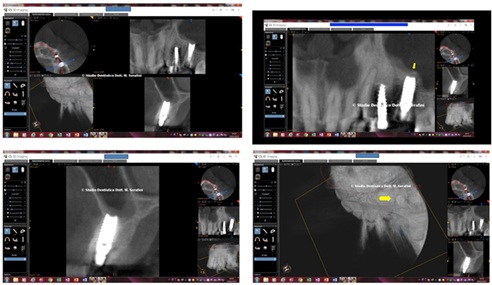

TC left side shown in figure 30.

Figure 30: TC left Side.

TC right side shown in figure 31.

Figure 31: TC Right Side.